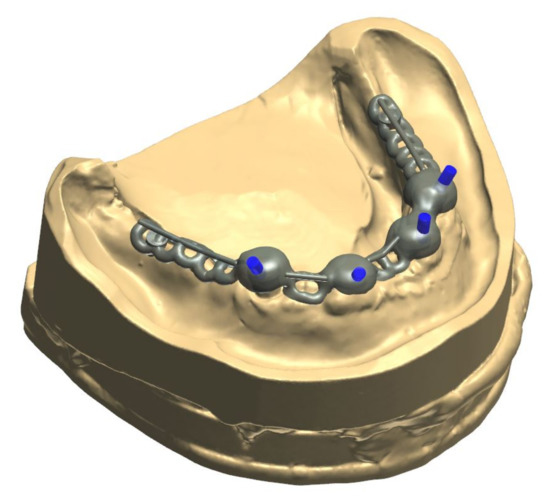

Figure 7.

Close-up screenshot of the digitally constructed alloy framework.

Figure 8.

Digitally constructed alloy framework on the digital model of the lower jaw.

The alloy framework employed in the current case was manufactured by selective laser sintering. Recent studies have highlighted that frameworks for removable dentures that had been fabricated by SLS feature an adequate precision [33,34,35,36]. However, to estimate the long-term outcome of these constructions, more clinical studies are required [22].

The healing time for the dental implants was four months. Subsequent to second-stage surgery and insertion of healing abutments (Figure 1), vestibular plastic surgery was performed employing an implant-supported dressing plate to produce sound and robust gingival tissues (Figure 2 and Figure 3). The first impressions were taken by using silicone-based impression materials (Kneton, Erkodent, Pfalzgrafenweiler, Germany) for the upper jaw and alginate for the lower jaw. The silicone-based material features constant mechanical properties and an extended setting time which is favourable for border moulding. For the lower jaw, an alginate impression material was used because it is easy to remove from the impression posts, which were inserted to indicate the implant position. A preliminary bite registration was performed using a special technique (Centric Tray, Ivoclar Vivadent, Schaan, Liechtenstein) (Figure 4) that simultaneously determines the preliminary vertical dimension. Cast gypsum models were prepared and digitalised in the dental laboratory and individual trays were designed and printed (3Shape, Copenhagen, Denmark; Flemingprint tray by DETAX, Ettlingen, Germany; Asiga MAX UV 3D Printer, Sydney, Australia) (Figure 5). An intraoral registration device based on needle-point tracing (Gnathometer M, Ivoclar Vivadent) was mounted on the trays. Following parallelisation of the plane of the upper jaw to the Camper`s plane and the bipupilar line, the vertical dimension was phonetically verified. The trays were used to take functional silicone impressions of the upper jaw in accordance with the suction effective mandibular complete denture (SEMCD) technique described by Abe [20,21]. Following border moulding, a functional impression of the lower jaw was taken by using polyether (Impregum, 3M, Saint Paul, MN, USA) impression material to transfer the implant position into the dental laboratory. Prior to this, the centric relation was determined with the intraoral registration device fixed onto the trays (Figure 6). In the dental laboratory, impressions and centric registration were digitalised. Subsequent to preparation of an implant master gypsum model with inserted stud attachments (Locator, Straumann), the alloy framework supporting the overdenture and housing of the attachment patrices was designed with CAM and produced using selective laser sintering (SLS) (FD MOG Flussfisch RPD, Flussfisch, Hamburg, Germany) (Figure 7 and Figure 8). Complete denture prostheses were designed in the upper and lower jaw by using CAD/CAM software (3Shape Dental system 2019 premium, Full denture design modul, Kopenhagen, Denmark) and the concept of a bilaterally balanced occlusion. The dataset was used to print try-in templates (Flemmingprint temp made by DETAX, Ettlingen Germany; Asiga MAX UV 3D Printer, Alexandria, Australia) (Figure 9). During the next appointment, the framework (Figure 10, Figure 11 and Figure 12) and templates were tried in separately (Figure 13) and the patient was satisfied with function and aesthetic appearance. Afterwards, the framework was stained with a pink opaquer, and the removable dentures and teeth were milled from pre-polymerised blanks (IvoBase CAD and SR Vivodent CAD, Ivoclar Vivadent, Schaan, Liechtenstein) using the dataset provided by the software (Figure 14). Subsequent to the milling process (vhf S2, vhf camfacture AG, Ammerbuch, Germany) (Figure 15), the teeth were inserted by hand. The polymeric overdenture and its supporting alloy framework were joined with a polymer (Pala X-Press, Kulzer, Hanau, Germany) and polished (Figure 16, Figure 17 and Figure 18).